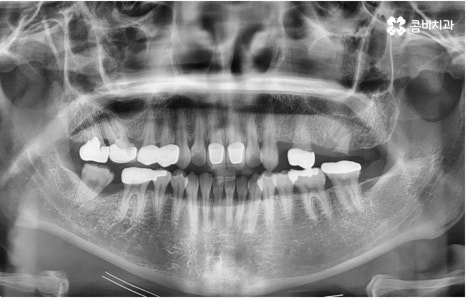

자연 치아를 살리기 위한 거의 마지막 단계의 보존 치료가 바로 신경치료, 재신경치료, 치근단절제술 등이며, 만약 치아재식술을 통해서도 살릴 수 없을 정도로 손상이 깊고 심하다면 해당 치아를 발치하고 임플란트를 통해 인공 치아로 대체해 줄 필요가 있습니다.

임플란트는 유치, 영구치 이후로 제 3의 치아라고 불리울 만큼 자연 치아의 상실에 대처하는 인공 치아 중에 가장 각광을 받고 있습니다. 저작력 회복이 80%에 가깝고 심미적으로 자신의 치아와 거의 다름없어 보이는 부분에서도 만족도가 높아 많은 분들이 찾고 있지만 식립 성공률과 안정적인 지속률에 크게 영향을 주는 올바른 위치 및 각도로의 식립을 무리하지 않게 진행하기 위해 술자의 높은 숙련도를 요하는 고난도의 수술이기 때문에 임상 경험이 많고 뛰어난 노하우를 갖추고 있는 담당의 선생님과 함께 하시는 것이 중요한 포인트라고 할 수 있어요.

관리의 측면에서 교합이 맞지 않고 치열이 똑바르지 않으면 음식물 찌꺼기가 잘 끼고 잇몸이 붓기 쉽기 때문에 교정 치료가 필요할 수도 있습니다. 씹기가 어렵고 안면비대칭이나 턱관절 통증을 유발하는 등 심각한 부정교합의 경우 기능적으로도 필요하지만 약간 삐뚤어지거나 치아 사이가 벌어진 경우 심미적으로도 한 번쯤 교정 치료를 생각해 보셨을 텐데요, 가격이나 기간, 나이 등 여러 가지 부분이 신경쓰여서 막상 시작하기에 부감을 느끼고 계셨다면 먼저 명동치과 에 내원하셔서 자신에게 필요한 교정 치료가 어떤 것인지 알아보시면 좋을 거예요. 골격적인 원인이 크지 않고 정도가 심하지 않다면 환자분들의 상황에 따라 부분 교정으로 보다 짧고 간편하게 진행하는 경우도 있으니 3D CT 와 같이 정밀 검진 기계를 갖춘 치과에서 숙련된 의료진에게 검진 및 상담부터 받아보시길 권유드리고 있습니다.